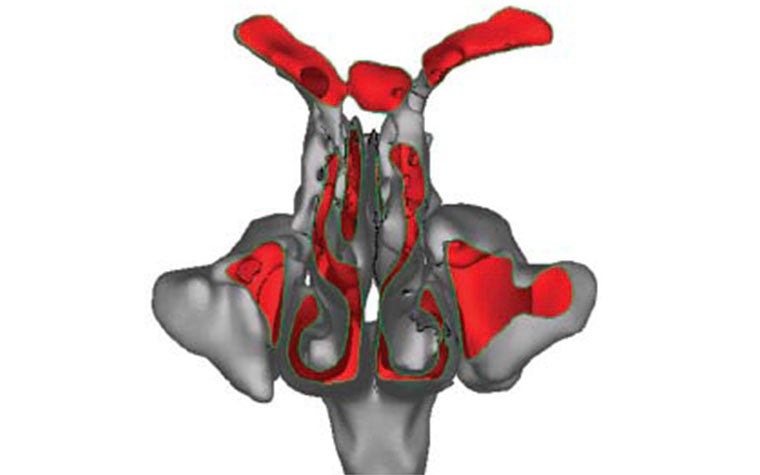

In order to simulate the airflow in the nasal cavity numerically, the volume needed to be parted into small cubes of equal size, also known as voxels. Their vertices, also called nodes, with their linking edges provide the volume mesh needed for the LBM computation. In order to generate this type of volume mesh from an STL surface mesh, Dr. Krause chose the open-source Common Versatile Multi-purpose Library for C++, the code of which is included in the OpenLB library.

Before the airflow could be simulated on a computer, Dr. Krause needed to specify the inflow and outflow regions, which are located at the trachea and the two nostrils. He distinguished them from the flow region and the wall of the nasal cavity by assigning certain different material numbers to the nodes of the volume mesh. Depending on their distribution, it becomes possible to initialize the simulation algorithm. Yet, the initialization process for LBM algorithms and their automatization pose a challenge since the algorithm setup for each node depends on the material numbers of all neighboring nodes.

Furthermore, for particular material number distributions, the initialization is not possible. These difficulties were overcome by a generic concept proposed and realized in the OpenLB project. This concept relies on sophisticated routines that allow the original voxel mesh to be modified where needed without changing its characteristics.